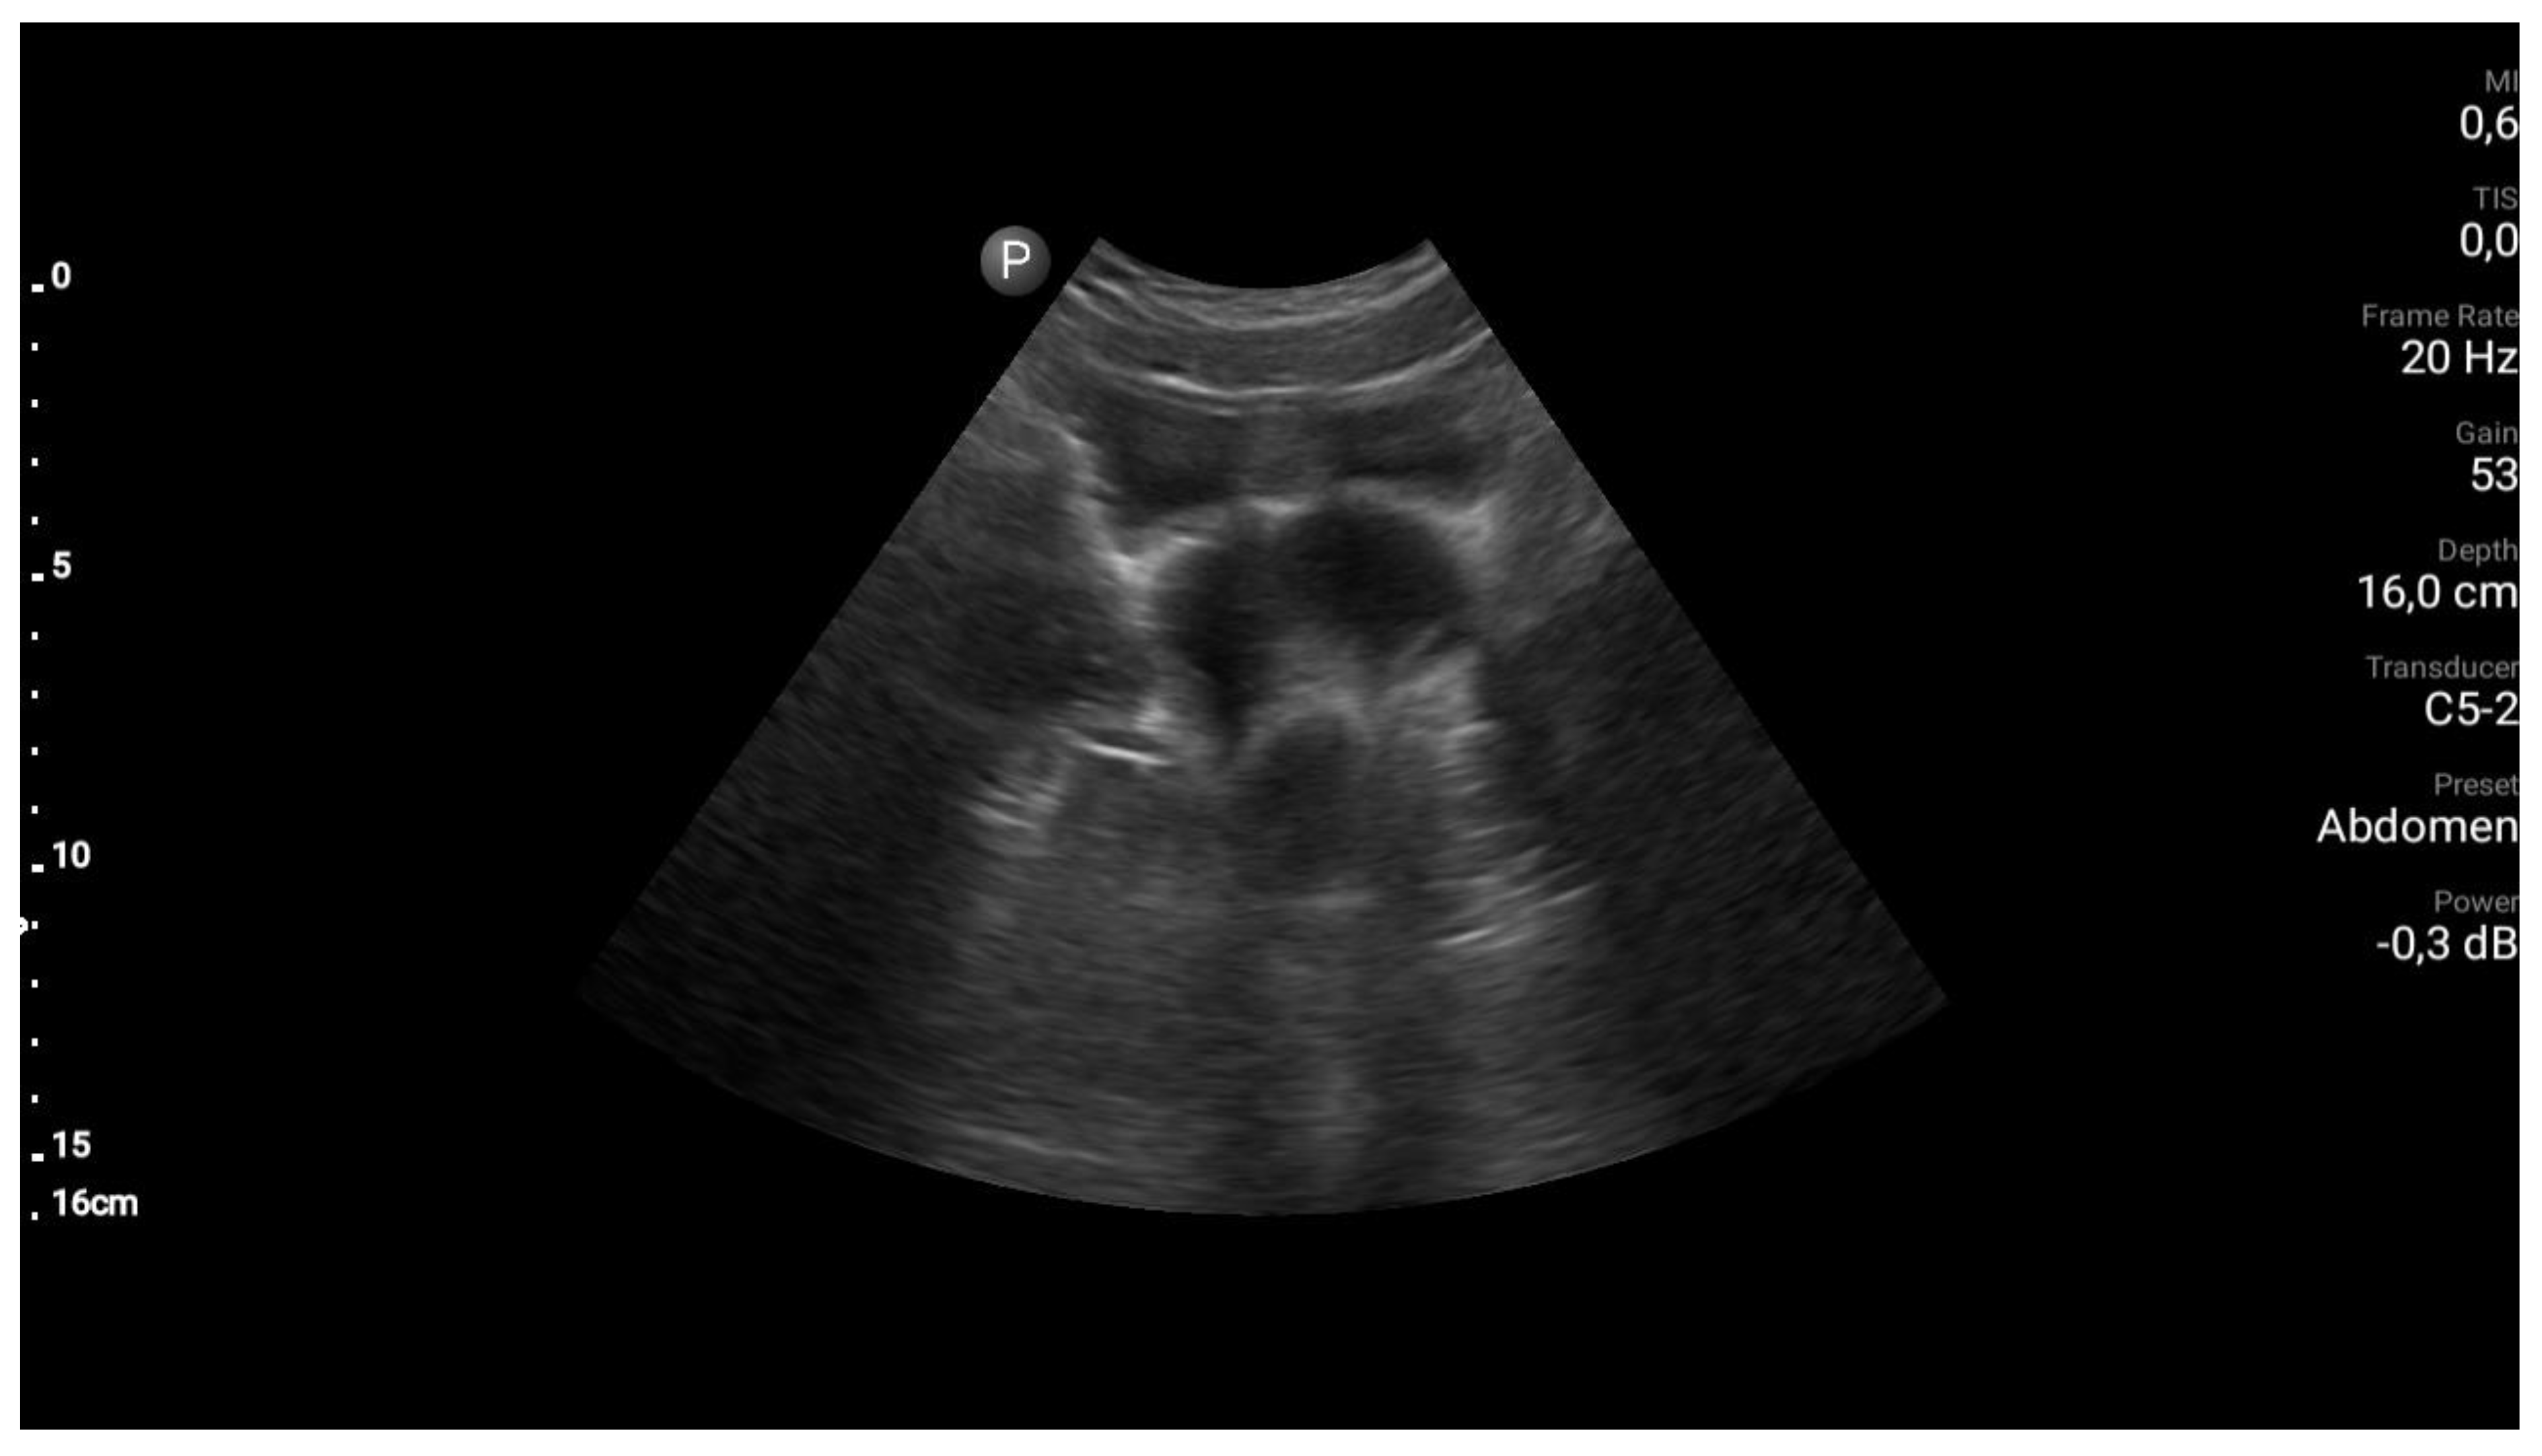

Step 1. Preoperative management Patients age (mostly occurs in young females), accurate history: time of first period, gradually increased symptoms, the appearance of symptoms during menarche, symptoms increase with each subsequent period, recurrent UTI, urinary disorders [8,9]. Perform physical examination. Next to the transabdominal US, transperineal and transrectal US can be useful in emergency situations to accurately access the place of abnormality [10]. MRI imaging should be considered as "gold standard in the diagnostic process [11]. Plan of the surgery and step by step proceeding is important while operating patients with urogenital abnormalities. As interdisciplinary collaboration of urologist and gynecologist is often necessary to treat correctly these patients. |

Step 3 Surgical management Surgery is necessary when acute abdominal symptoms are present. “Wait and see” approach is only possible when the clinical situation allows it. Perform laparoscopy and vaginoscopy in order to achieve the correct diagnosis and treat concomitant hematosalpinx and endometriosis [14]. Intraoperative US is helpful to evaluate the place of resection. Unnecessary lengthening the time to diagnosis, contributes to unindentent consequence. |